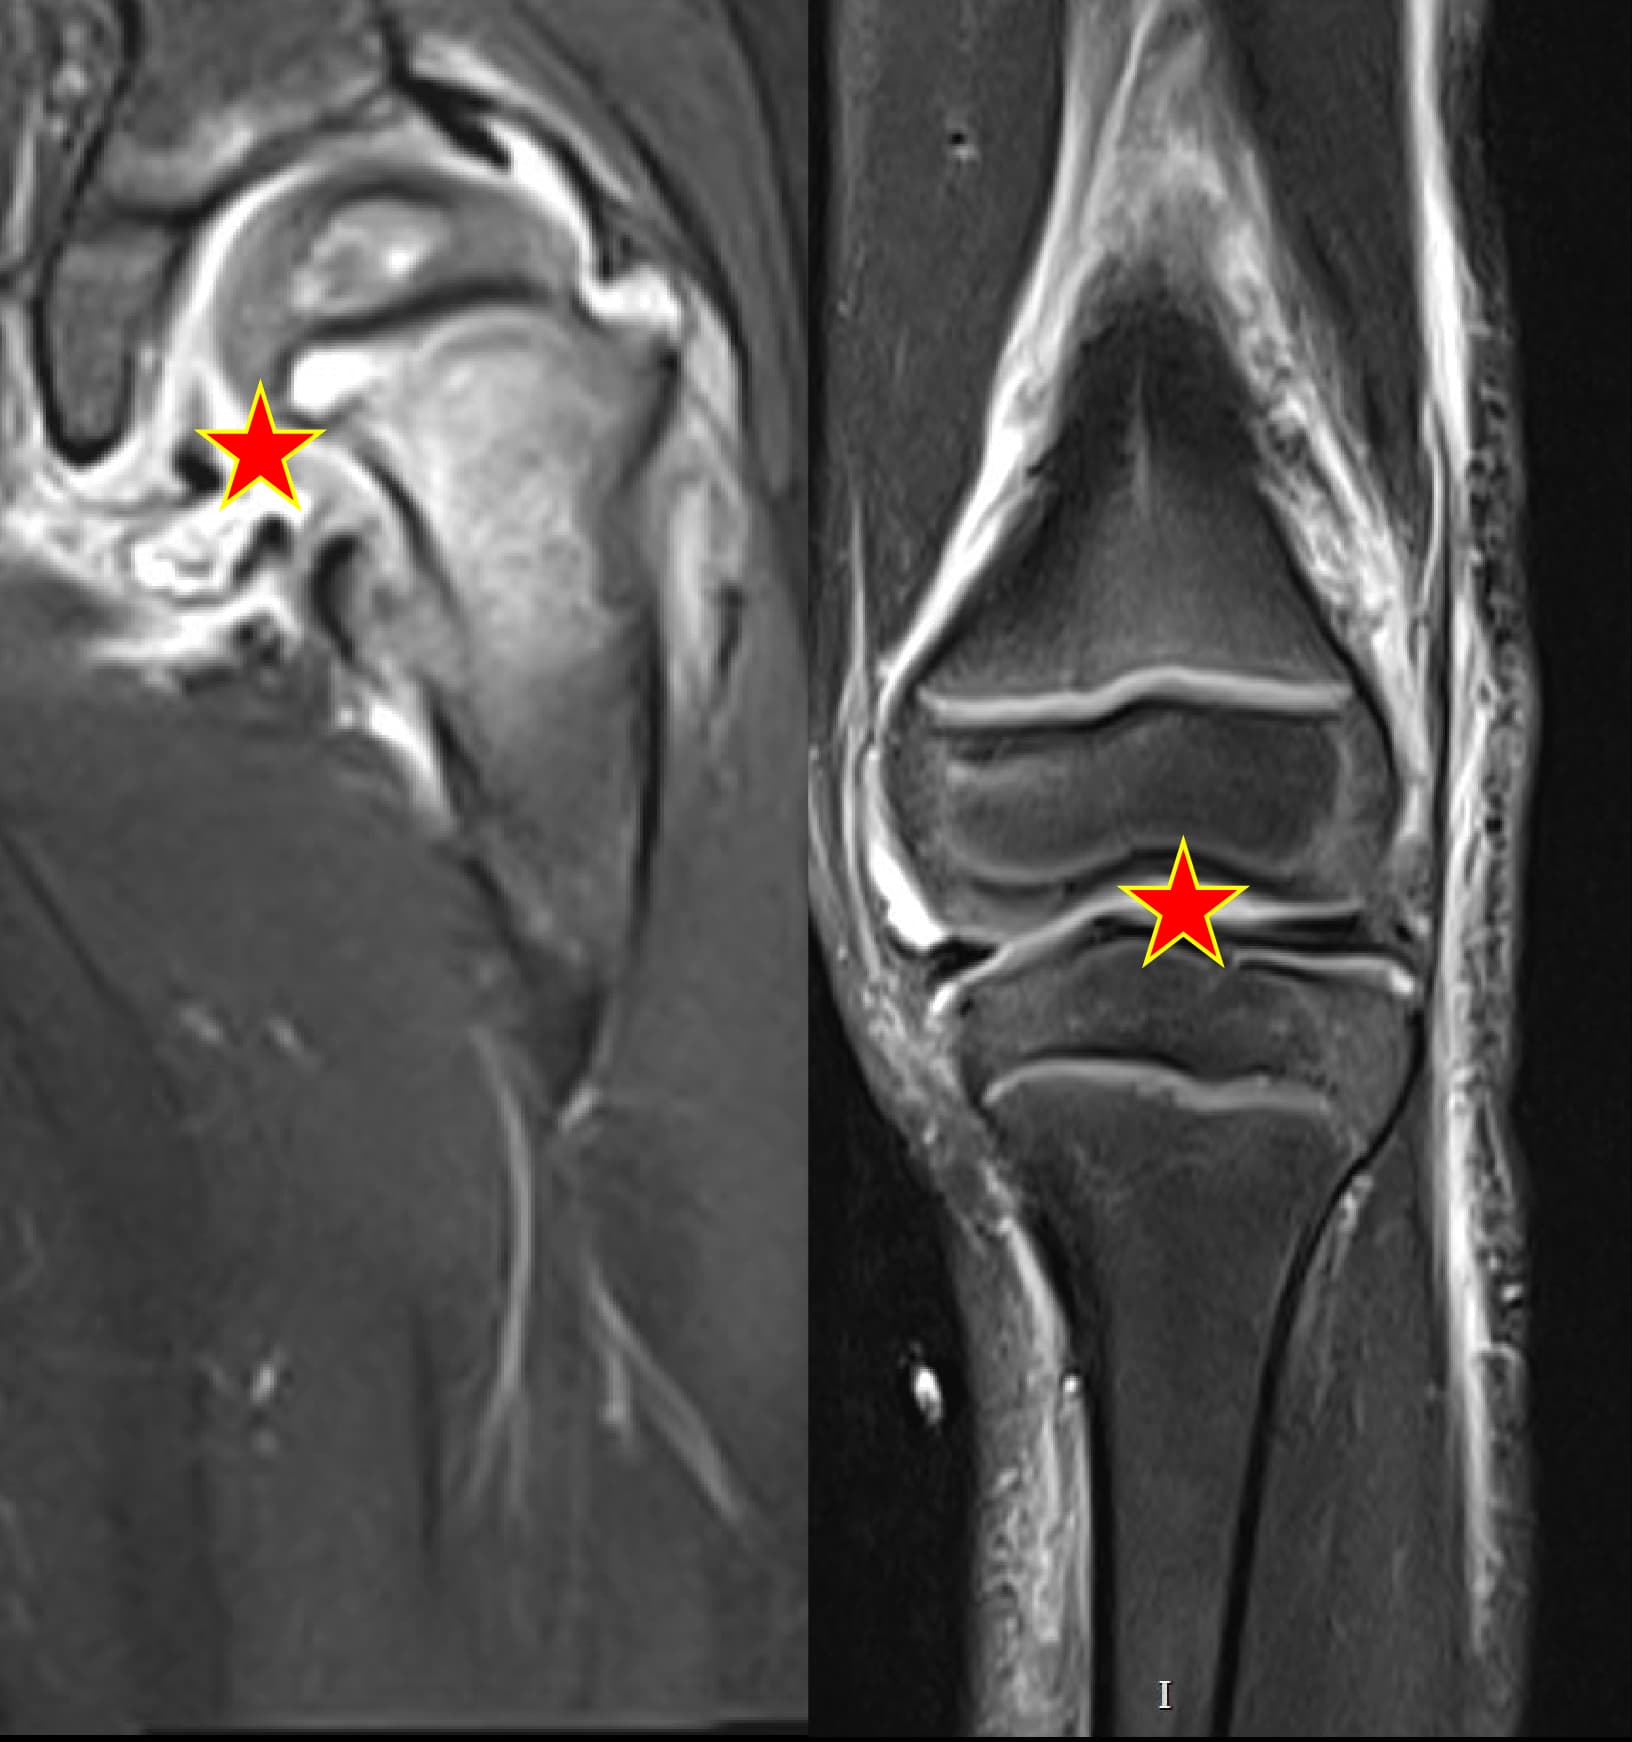

Septic arthritis

Hip & knee arthritisMRI case galleryClinical insights

Septic arthritis cases